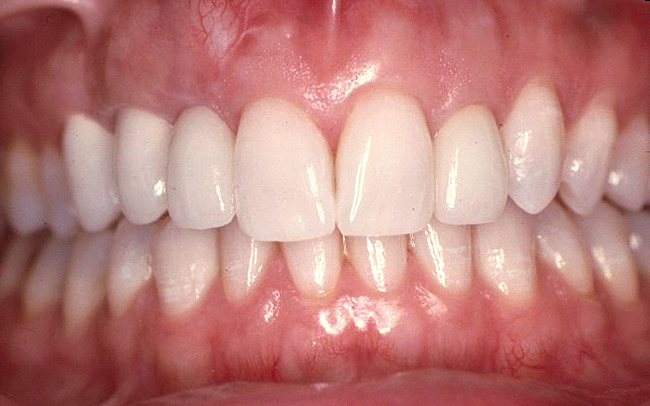

It is usually desirable to maintain shallow rather than deep probing depths around teeth for multiple reasons: shallow depths facilitate supragingival hygiene, which impacts the subgingival microflora; there is less bleeding on probing; at shallower sites it is easier to instrument root surfaces; there is less predisposition for disease progression; and shallow depths are better forecasters of periodontal stability.13 Pertinently, periodontal surgery is often done to reduce or eliminate deep probing depths.14 However, a usual consequence of periodontal surgery is recession of the gingiva and interdental papillae, which may create undesirable “black triangles” between teeth. Therefore, resective procedures that create an unesthetic gingival topography are contraindicated on teeth that have a questionable prognosis in the esthetic zone. In addition, surgical procedures may result in large interdental embrasures, which are plaque retentive and may cause increased thermal sensitivity (Figure 1).

Figure 1  Periodontal surgical procedures on compromised teeth to eliminate deep probing depths usually result in recession interdentally and facially.

Figure 1